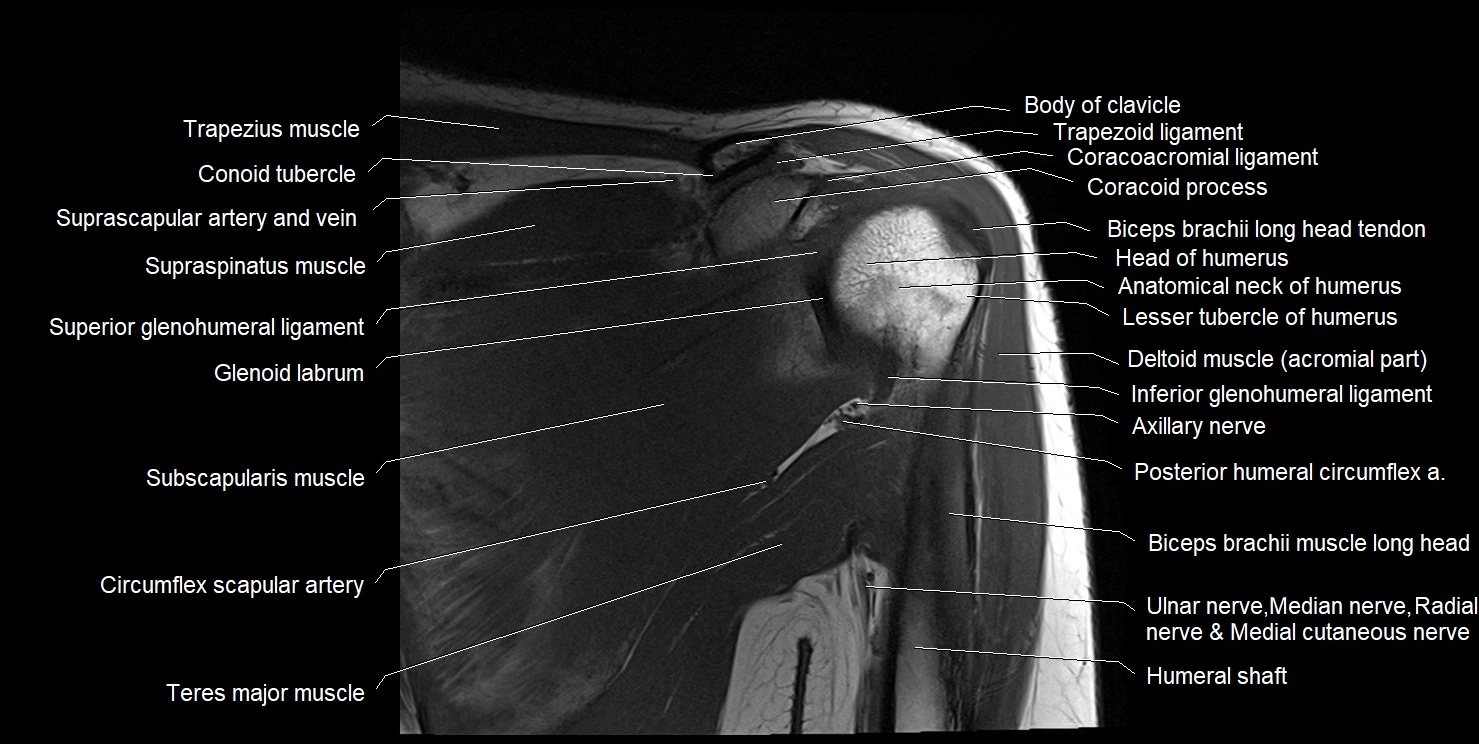

CT image

image